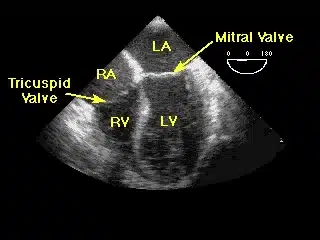

تخطيط صدى القلب ، والمعروف أيضاً باسم إيكو القلب ، هو فحص غير مؤلم يستخدم لتشخيص تشوهات القلب مثل تلف أنسجة القلب بسبب النوبة القلبية، أو ضعف أداء صمامات القلب. يستخدم تخطيط صدى القلب ( إيكو القلب ) الموجات فوق صوتية لتصوير القلب ، وتردد هذه الموجات لصدى القلب. يمكنهم عرض شكل وحجم وحركة الأذينين والبطينين والصمامات في القلب. يمكن أن يُظهر تخطيط صدى القلب أيضًا تدفق الدم عبر القلب.